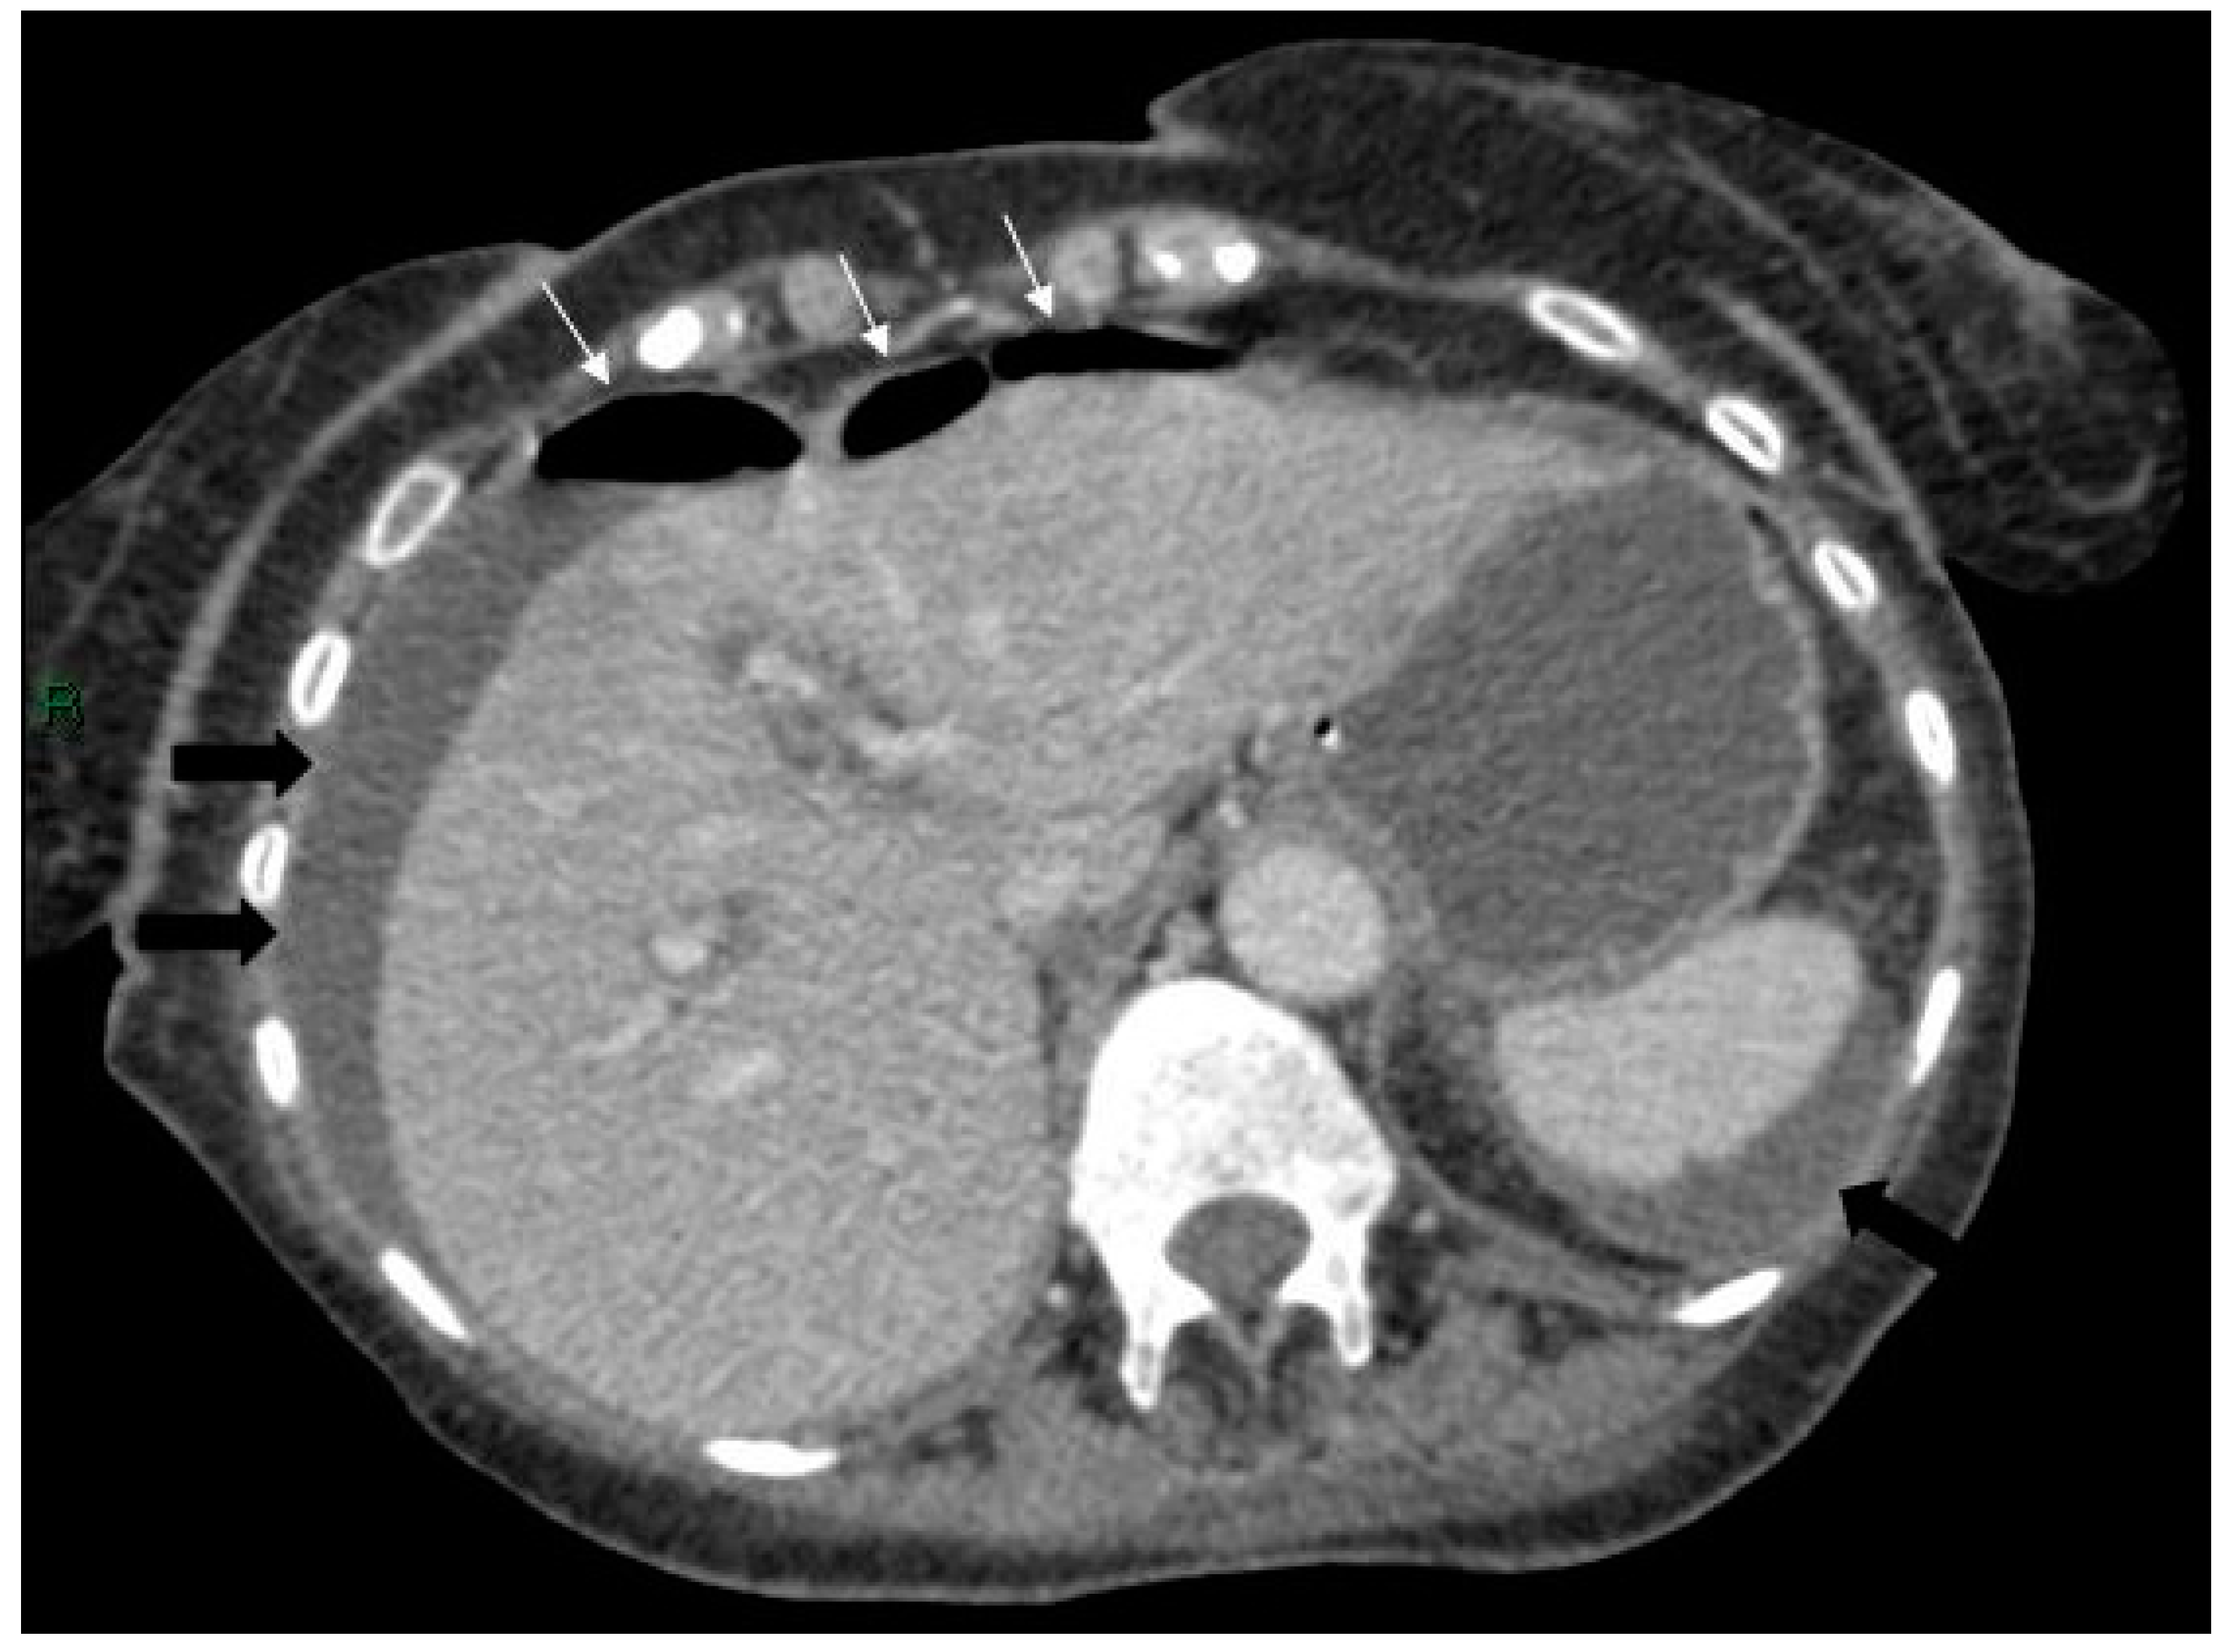

Figure 1.

Axial post-contrast computed tomography (CT) scan of the upper abdomen showing a large pancreatic pseudocyst with the stomach (arrows) stretched anteriorly over it.